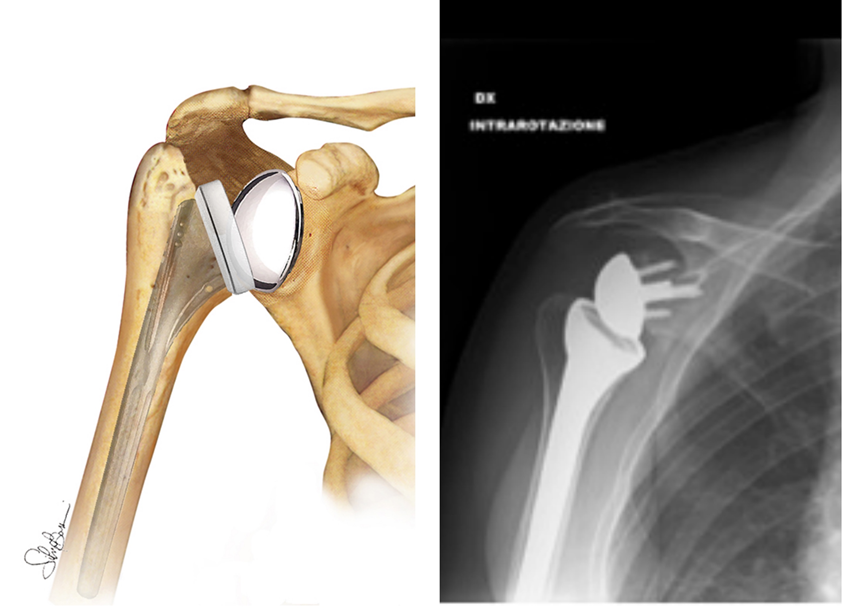

- Endoprotesi di spalla: a seconda della condizione della spalla, il chirurgo potrebbe sostituire solo la testa omerale. Questa procedura è chiamata emiartroplastica. In una emiartroplastica tradizionale, la testa omerale viene sostituita da una componente protesica metallica costituita da uno stelo sul quale viene adagiata una sfera, riproducendo cosi le normali componenti anatomiche. L’emiartroplastica viene consigliata quando la testa omerale è gravemente degenerata ma le restanti componenti articolari sono normali.

- Protesi inversa di spalla (fig. 9): un’altra opzione è rappresentata dalla protesi inversa di spalla, indicata per soggetti che presentano: (a) cuffia dei rotatori gravemente lesionata con perdita della forza e dell’arco di movimento; (b) articolazione gravemente artrosica; (c) fallimento di un precedente intervento di protesi totale di spalla. Importante chiarire che per questi soggetti all’intervento può seguire persistenza del dolore e una non totale riacquisizione dell’arco di movimento, soprattutto in abduzione. Nella protesi inversa di spalla, le convessità e le concavità articolari vengono invertite. Ciò significa che una sfera di metallo viene fissata alla glena e una superficie concava sostituisce la testa omerale.